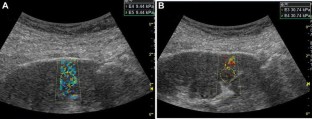

Fig. 2